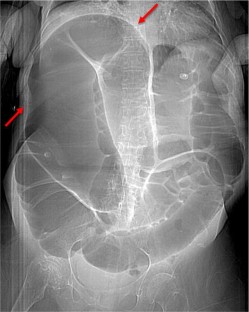

Coffee bean sign

Fig. 1

Chakraborty, A., Ayoob, A. & DiSantis, D. Coffee bean sign. Abdom Imaging 40, 2904–2905 (2015). https://doi.org/10.1007/s00261-015-0402-3

• Ischemia

• Perforation

• Closed Loop